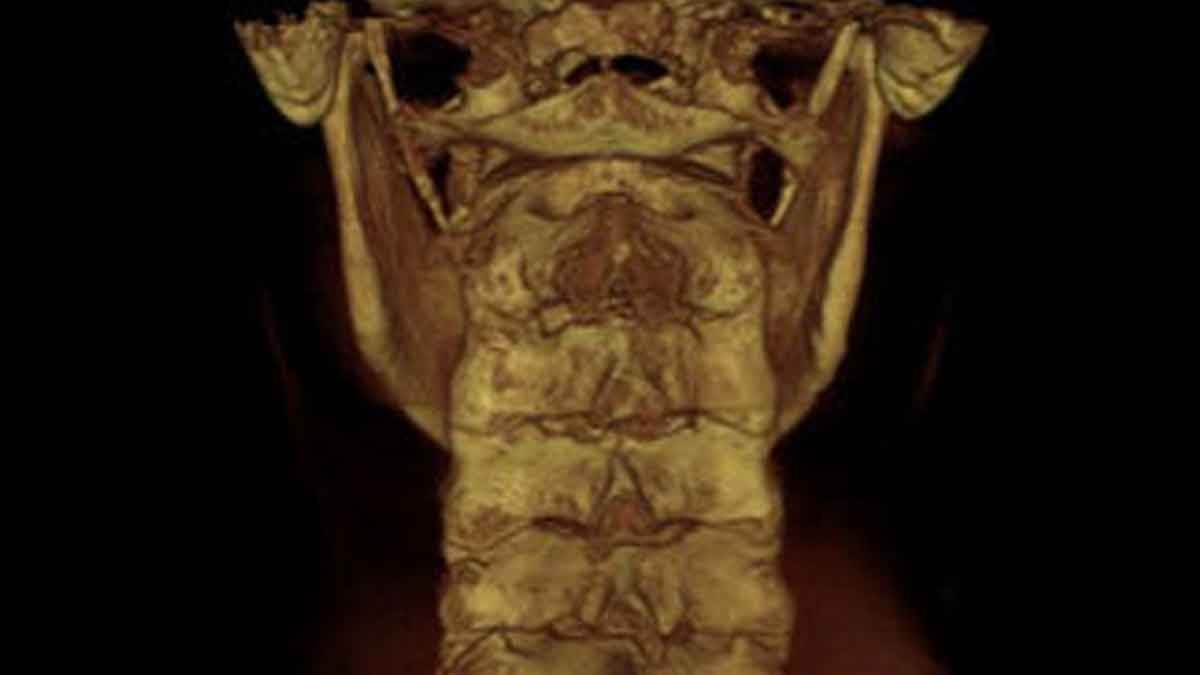

To see what CBCT images look like check out this video where Dr. Hall explains CBCT imaging technology and then goes over some of the views. Also, below you will find pictures of CBCT technology and real-life examples of articular spinal misalignments.

SAGITTAL VIEW OF UPPER CERVICAL SPINE

This view allows the doctor to assess the neural canal, the foramen magnum, and the longitudinal direction of the joints on the left and right that are on the bottom of the skull called the occipital condyle.